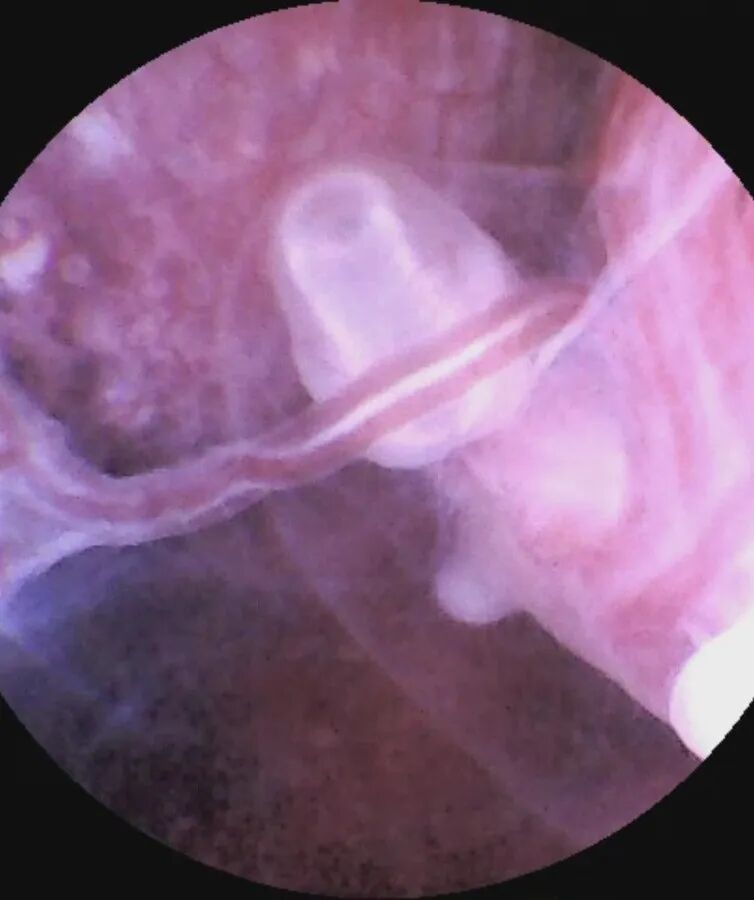

05.无痛可视人流技术

△无痛可视人流技术

妇科中心开展可视人流技术,通过可视人流设备全程直视,精准定位孕囊位置,定点清除妊娠组织,精细化终止妊娠,避免对子宫内膜的过度刮拭与损伤,降低子宫穿孔、宫腔黏连等并发症的风险,达到呵护女性子宫、保护生育力、关爱女性健康的目的。